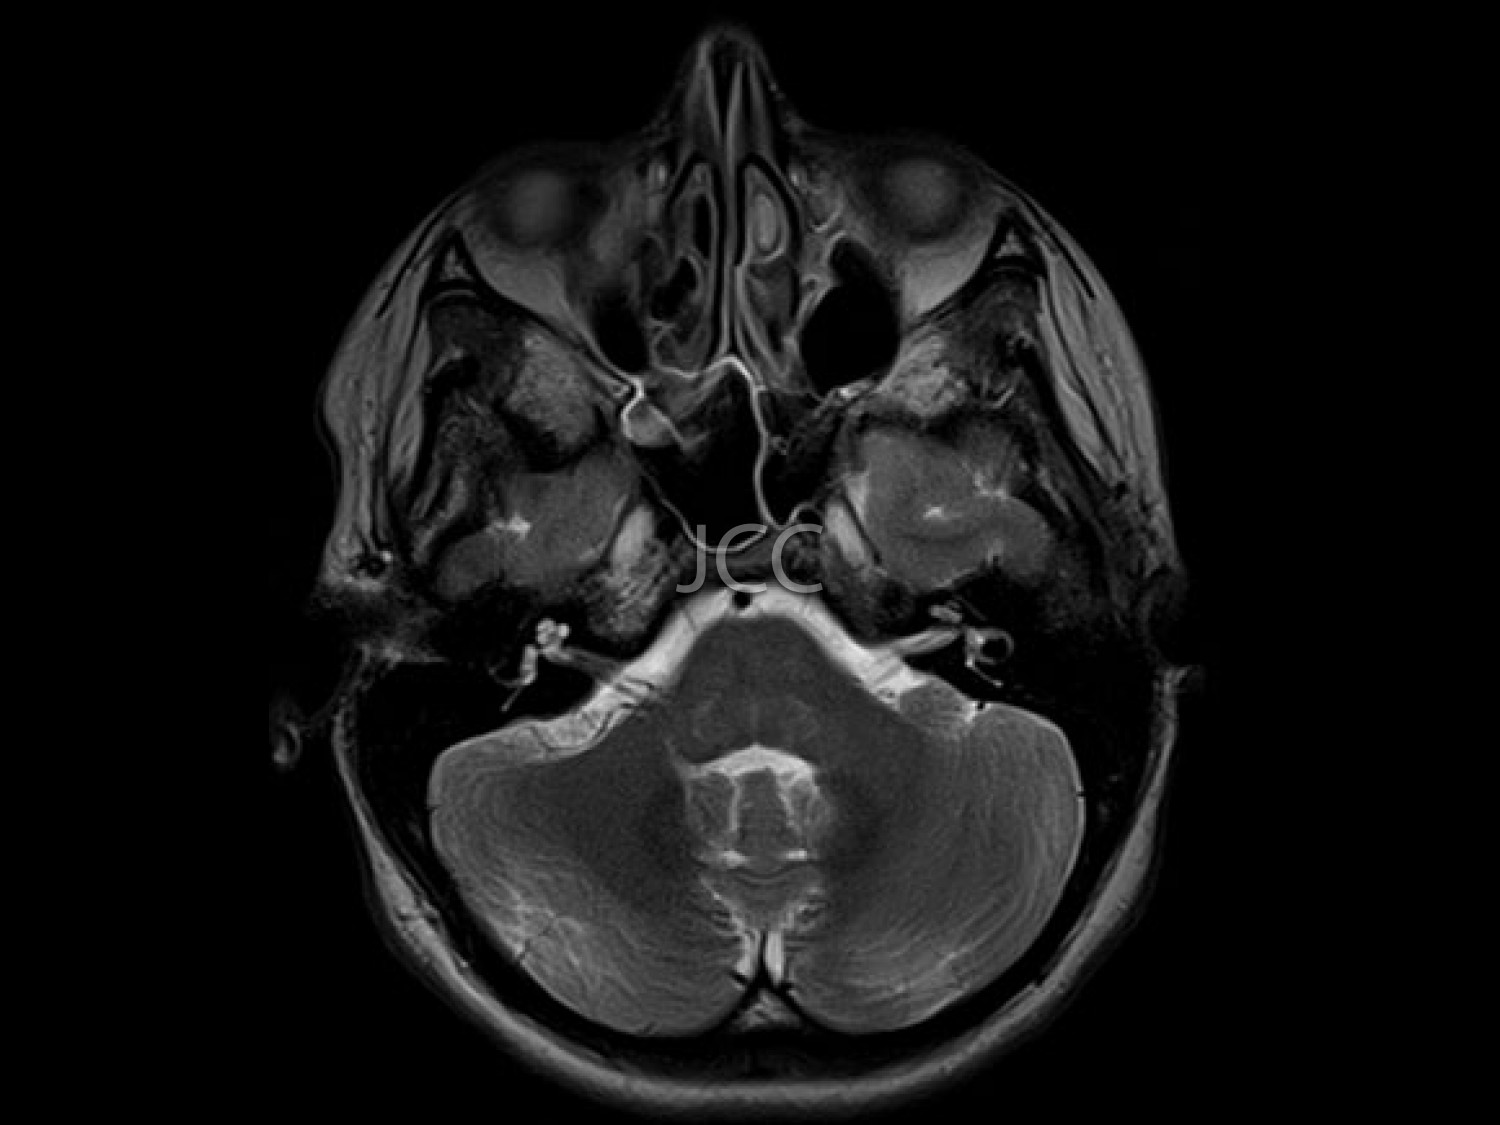

O AVC (acidente vascular cerebral), constitui uma causa de morte importante e sobretudo uma causa de grande incapacidade, particularmente no idoso. Subjacente a esta situação, está a patologia vascular devido ao estreitamento ou bloqueio completo das carótidas, vasos cerebrais (AVC isquémico), ruptura de aneurisma ou malformação vascular cerebral ou hemorragia secundária à hipertensão arterial (AVC hemorrágico). Na maior parte das situações não há sintomas que antecedam a instalação do AVC.

A angiografia das carótidas por TC, utilizando tecnologia de alta resolução e baixa dose de radiação, constitui o método não invasivo mais apurado, na avaliação das artérias carótidas e vertebrais, ou seja, as artérias que transportam o sangue para o cérebro. A redução do calibre por deposição de colesterol (placas) das carótidas e artérias vertebrais, é facilmente demonstrada por este método, bem como eventuais aneurismas das artérias cerebrais. A ressonância magnética permite a correcta demonstração e caracterização das malformações vasculares cerebrais, bem como a detecção precoce de inúmeras outras patologias cerebrais.